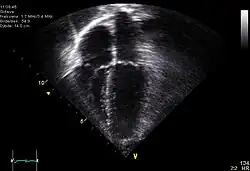

- konvexních – sondu tvoří konvexní (vypouklá) řada měničů, obraz má tvar kruhové výseče

- sektorových – ultrazvukový paprsek je postupně vychylován buď mechanicky nebo elektronicky, obraz má tvar široké kruhové výseče